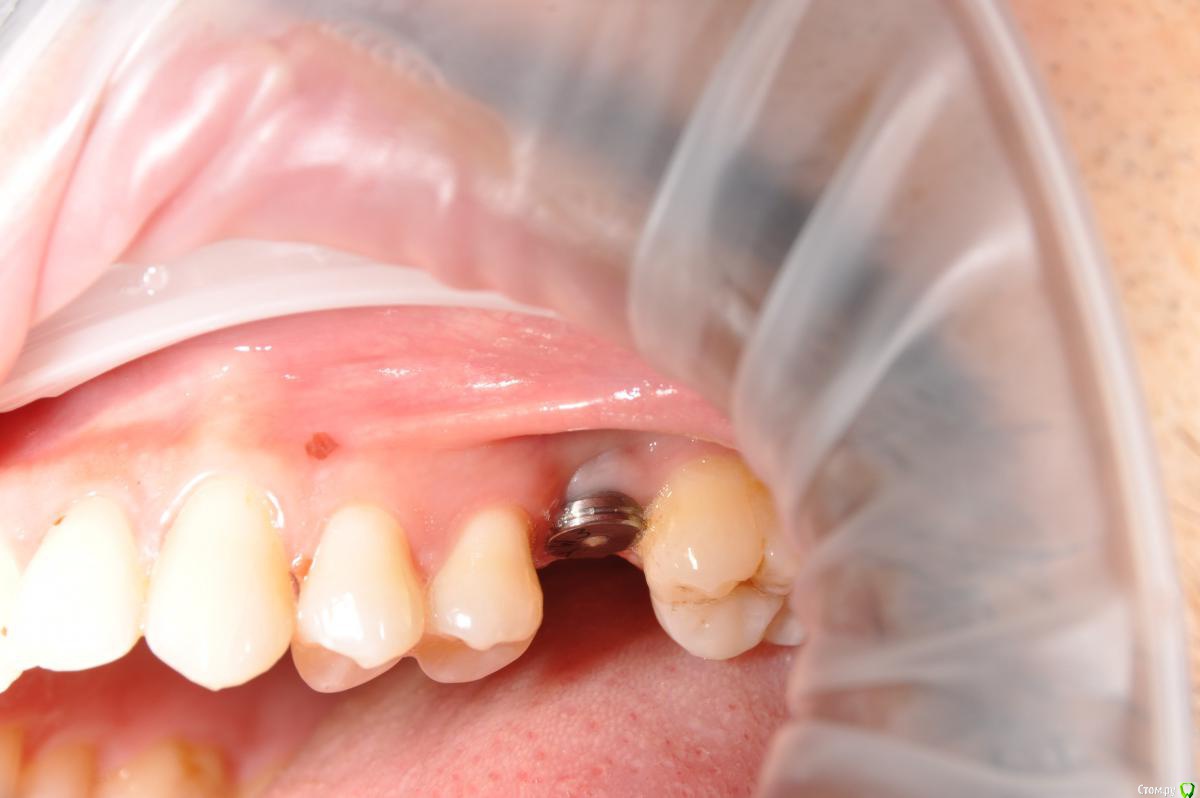

kamranchick Опубликовано 12 сентября, 2018 Автор Поделиться Опубликовано 12 сентября, 2018 Вот) Ссылка на комментарий

Евгений Ходыкин Опубликовано 12 сентября, 2018 Поделиться Опубликовано 12 сентября, 2018 Нуу...в общем... сам всё понимаешь))) Ссылка на комментарий

kamranchick Опубликовано 12 сентября, 2018 Автор Поделиться Опубликовано 12 сентября, 2018 Нуу...в общем... сам всё понимаешь))) что лучше ходить с формиком?)) Ссылка на комментарий